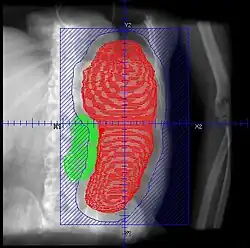

• Patients should be continuously monitored, and fields adjusted with shrinking spleen

• Retrospective. 22 courses for 19 patients. Total dose 1.5 - 8.0 Gy (median 4.5 Gy), fractional dose 0.25 - 1 Gy delivered weekly or twice weekly. AP/PA. Median field reduction 25%